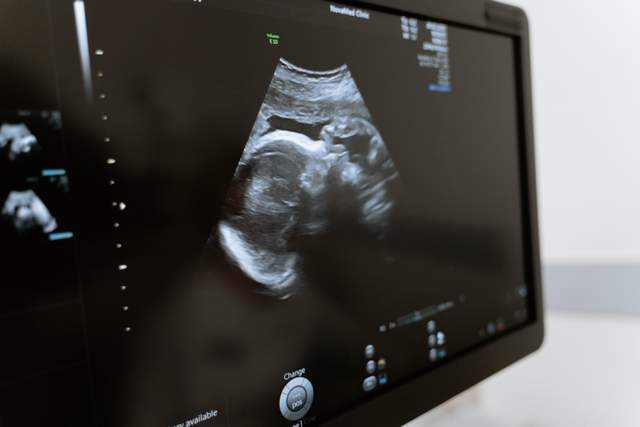

Как эмигрантке наблюдать беременность в Польше: советы врача из Украины

Многие женщины, которые переехали в Польшу, готовятся рожать в чужой стране. Некоторые протоколы ведения беременности отличаются от тех, которыми пользуются врачи в Украине. Гинеколог Галина Драч рассказала о главных моментах, которые нужно знать беременной эмигрантке.